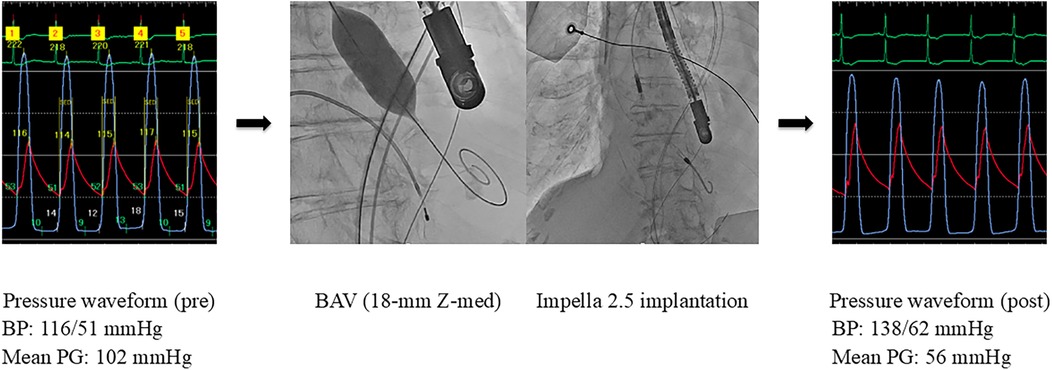

The pathology was considered CS associated with reduced cardiac output due to severe AS. Emergent BAV was performed using an 18-mm Z-Med balloon (NuMED, Inc., Hopkinton, NY), resulting in a reduction in the aortic valve PG from 102 to 56 mmHg. However, low cardiac output persisted with a CO of 1.8 L/min and a CI of 1.4 L/min/m2. Subsequently, an Impella 2.5 device was implanted, selected because of poor vascular access and small body surface area of 1.2 m2. These interventions resulted in an increase in CO to 2.3 L/min, CI to 1.7 L/min/m2, and blood pressure to 138/62 mmHg (Figure 2). As the patient's cardiac function showed gradual improvement and hemodynamic parameters stabilized, the Impella device was removed on day 6. In the multidisciplinary heart team discussion, it was determined that the patient was at high surgical risk (STS score: 32.2%, Clinical Frailty Scale score: 2, Katz Index: 5), and TAVR was planned. On day 9, elective TAVR with a 23-mm SAPIEN 3 valve was successfully performed.

Figure 2

Hemodynamic improvement after BAV and Impella support (Case 2). BAV, balloon aortic valvuloplasty; BP, blood pressure; PG, pressure gradient.